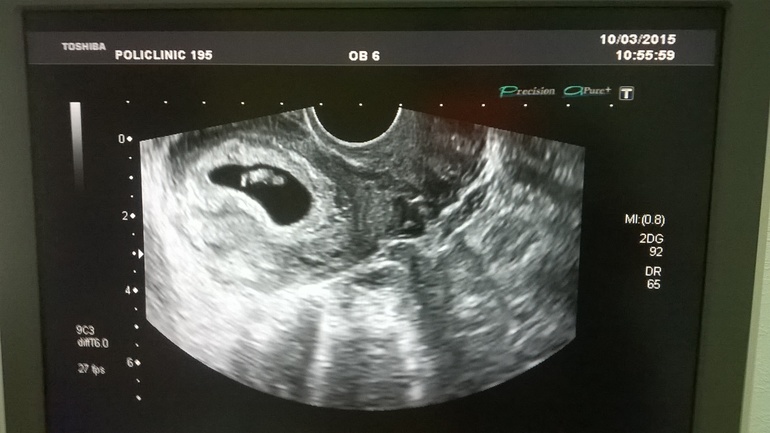

УЗИ, КТГ, доплерУтром проснулась, пошла в ванну и обнаружила коричневые выделения, отвела сына в сад и побежала на УЗИ, оно у меня сегодня назначено было. Сказала узистке, она все посмотрела и сказала, что все в порядке, просто небольшая гематома. Беременность 7 недель и 3 дня по месячным, а плод соответствует 6 нед. и 7 дн, сердце бьется 128 ударов, размер 19 мм 💓 Все хорошо у нас )) на прием теперь 13 числа

может пя 19мм а не плод сам? у меня такой был в 8,5 недель когда он уже на человечка похож

Незнаю, просто сказали 19 мм ))) может и плодное яйцо, на руки ничего не дали, только фото. Вот у врача все распрошу.

Это хорошо, когда все хорошо))) надо же на 6 нед и 3 дня 19мм. Я была как раз в 6 нед и 3 дня и моя крошка была 5 мм. Узистка сказала, что это и есть на 6 недель- просто нижняя граница нормы. А с сыном ходила в 7 недель и 2 дня и он был 14 мм, так врач сказала, что он даже большой!